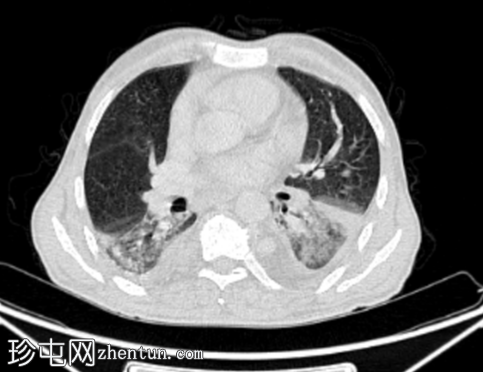

CT

轴位增强扫描(C+)门静脉期

双侧下叶肺实变,FDG摄取增高(SUVmax 7),可能为炎症性

心脏扩大和轻度双侧胸腔积液。